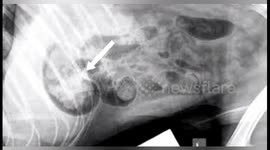

But soon after he was sick and after becoming more unwell Rebecca took Rylo to the vets, where an x-ray revealed a 12in plastic arrow inside his stomach.

Vets sedated him and pulled it out through his mouth and thankfully he is recovering well.

"They x-rayed him and rang me to say that I was not going to believe what the problem was," Rebecca said. "